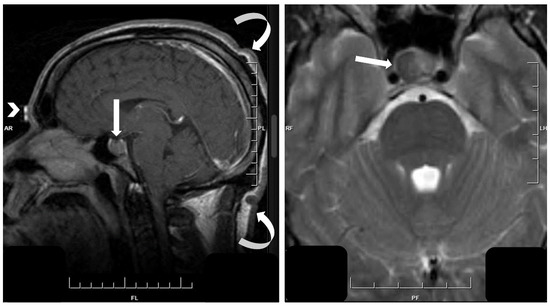

- Asa, S.L.; Mete, O. Hypothalamic Endocrine Tumors: An Update. J. Clin. Med. 2019, 8, 1741. [Google Scholar] [CrossRef]

- Asa, S.L.; Scheithauer, B.W.; Bilbao, J.M.; Horvath, E.; Ryan, N.; Kovacs, K.; Randall, R.V.; Laws, E.R.; Singer, W., Jr.; Linfoot, J.A.; et al. A case for hypothalamic acromegaly: A clinicopathological study of six patients with hypothalamic gangliocytomas producing growth hormone-releasing factor. J. Clin. Endocrinol. Metab. 1984, 58, 796–803. [Google Scholar] [CrossRef]

- Felix, I.; Bilbao, J.M.; Asa, S.L.; Tyndel, F.; Kovacs, K.; Becker, L.E. Cerebral and cerebellar gangliocytomas: A morphological study of nine cases. Acta Neuropathol. 1994, 88, 246–251. [Google Scholar] [CrossRef]

- Puchner, M.J.A.; Lüdecke, D.K.; Saeger, W.; Riedel, M.; Asa, S.L. Gangliocytomas of the sellar region—a review. Exper. Clin. Endocrinol. 1995, 103, 129–149. [Google Scholar] [CrossRef] [PubMed]

- Cossu, G.; Daniel, R.T.; Messerer, M. Gangliocytomas of the sellar region: A challenging diagnosis. Clin. Neurol. Neurosurg. 2016, 149, 122–135. [Google Scholar] [CrossRef] [PubMed]

- Araki, Y.; Sakai, N.; Andoh, T.; Yoshimura, S.; Yamada, H. Central neurocytoma presenting with gigantism: Case report. Surg. Neurol. 1992, 38, 141–145. [Google Scholar] [CrossRef]